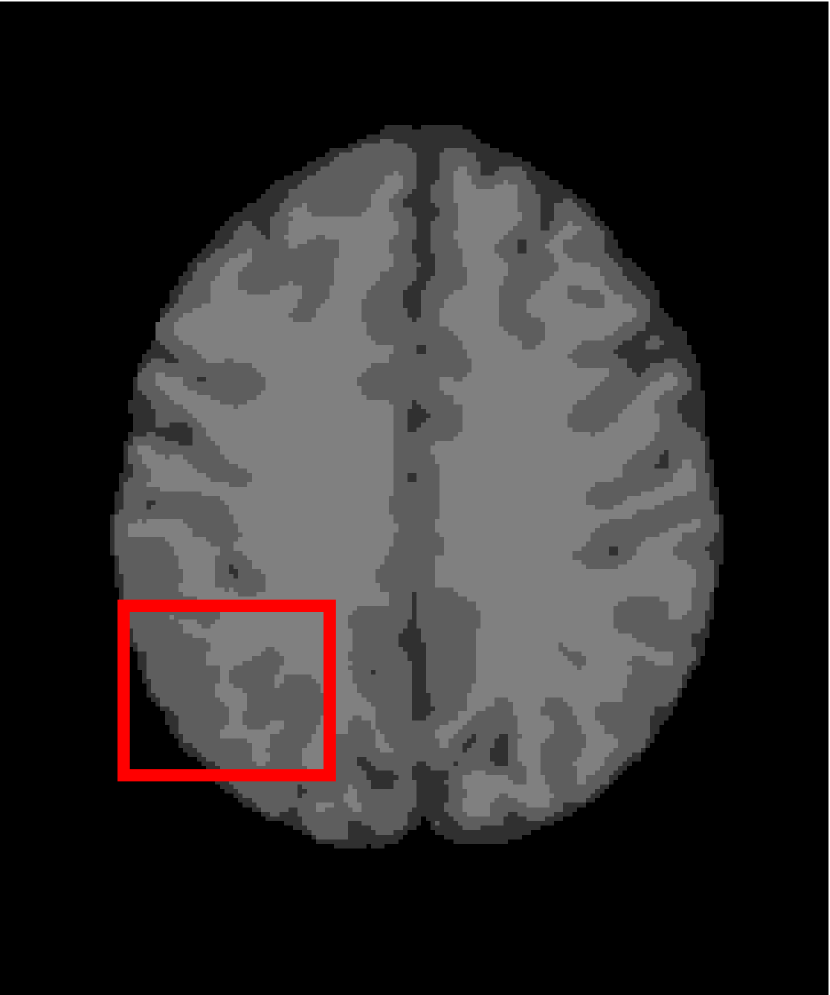

In the second experiments, we segment two medical images coming from a simulated brain database (BrianWeb): http://www.bic.mni.mcgill.ca/brainweb/. The two images are generated by T1 modality with slice thickness of 1mm resolution, 9% noise and 20% intensity non-uniformity. Here, the two images are represented two slices in the axial plane with the sequence of 100 and 110. Moreover, there are golden standard segmentations in the dataset. We set the numbers of clusters to 4. The visual comparisons are illustrated in Figs. 6 and 7.

Figure 7: Segmentation results for the second medical image. From (a) to (l): ground truth, noisy image and results of FCM_S1, FCM_S2, FGFCM, FLICM, KWFLICM, ARKFCM, FRFCM, WFCM, DSFCM_N, and LRFCM.

By focusing on the marked red square in Figs. 6 and 7, we easily find that FCM_S1, FCM_S2, FGFCM and ARKFCM are sensitive to noise. FLICM and KWFLICM are vulnerable to severe intensity inhomogeneity. FRFCM brings overly smooth results due to the use of gray level histograms. WFCM and DSFCM_N cause several contours to change. However, LRFCM acquires clear contours and suppresses noise adequately. Moreover, we find that the segmentation result of LRFCM is closer to ground truth.